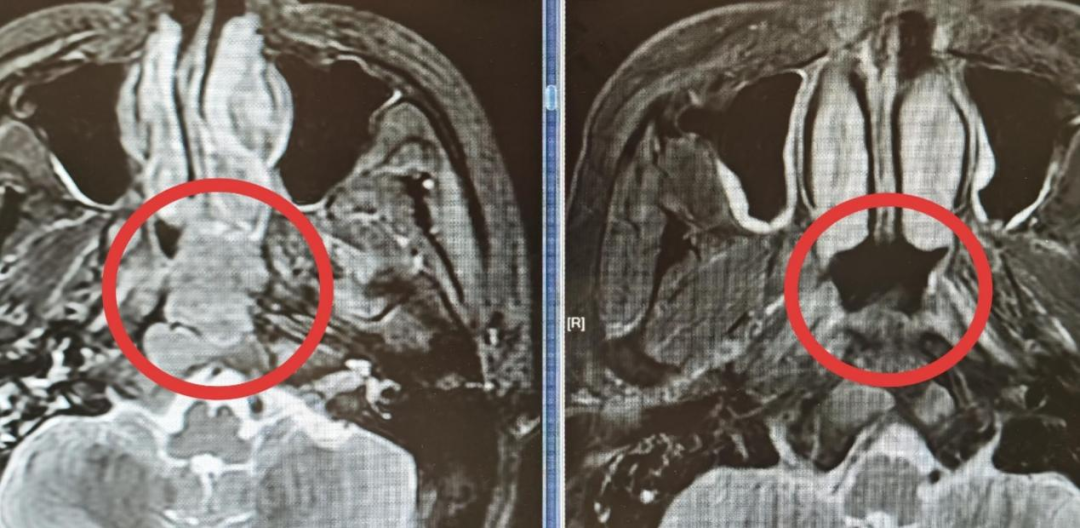

▲小黄的CT影像

第二步:初见成效治疗起效非常直观。在第1个周期化疗结束后,小黄第二次来医院时,自己都感觉到了明显的变化:头痛大幅减轻,往右看的时候,眼球也能稍微转过去一些了。复查的CT印证了他的感受:肿瘤已经开始退缩。 随着治疗周期稳步推进,小黄的右眼活动功能基本恢复正常,头痛也彻底消失了。

▲患者之前前后CT影像